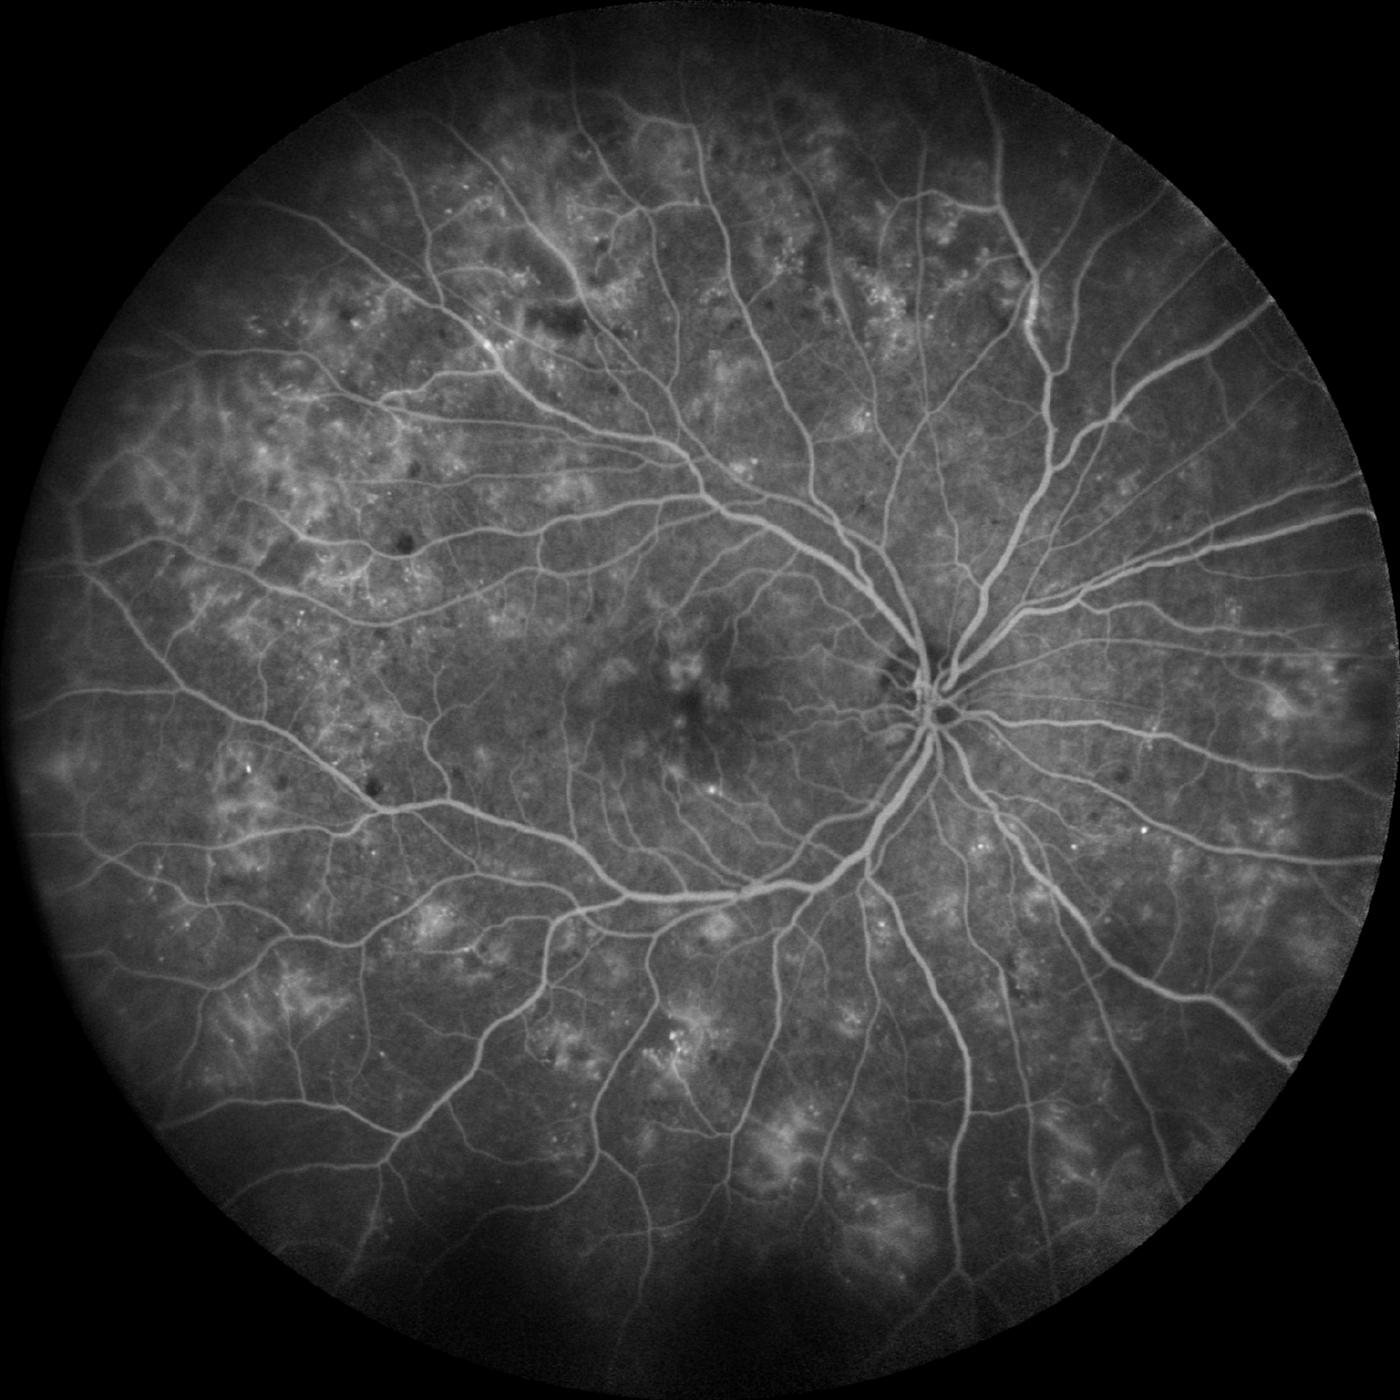

Flourezeinangiographie bei schwerer diabetischer Retinopathie

Regelmäßige Augenuntersuchungen sind entscheidend, um diabetische Retinopathie frühzeitig zu erkennen und zu behandeln. Mit Hilfe moderner bildgebender Verfahren wie der Optischen Kohärenztomographie (OCT) und der Fluoreszenzangiographie (FAG) können Netzhautschäden präzise diagnostiziert werden. Eine gute Blutzuckerkontrolle und ein gesunder Lebensstil sind ebenfalls wichtige Faktoren, um das Risiko von diabetischen Augenveränderungen zu verringern.

Diabetes kann schwerwiegende Auswirkungen auf die Augen haben und eine Vielzahl von Komplikationen verursachen. Eine der häufigsten Augenerkrankungen bei Diabetikern ist die diabetische Retinopathie. Diese entsteht durch Schäden an den Blutgefäßen der Netzhaut, was zu Sehverlust und im schlimmsten Fall zur Erblindung führen kann. Erste Symptome können verschwommenes Sehen, dunkle Flecken oder Linien im Sichtfeld und Schwierigkeiten beim Erkennen von Farben sein.